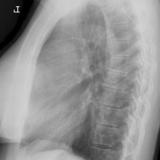

Case 8b Thymoma Lat

Date: 03/27/2009